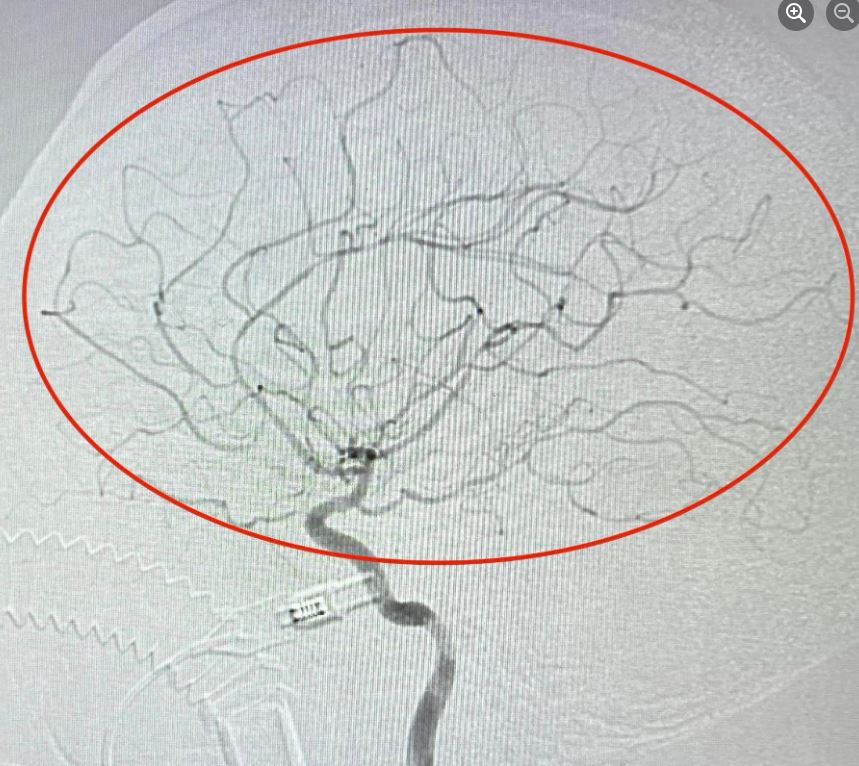

Bệnh viện Thống Nhất cứu thành công cụ bà đột quỵ do tắc động mạch cảnh trong

Bệnh viện Thống Nhất vừa cấp cứu, điều trị thành công bệnh nhân nữ 71 tuổi, bị nhồi máu não bán cầu trái giờ thứ 2 do tắc động mạch cảnh trong trái.